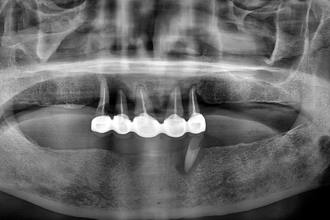

임플란트